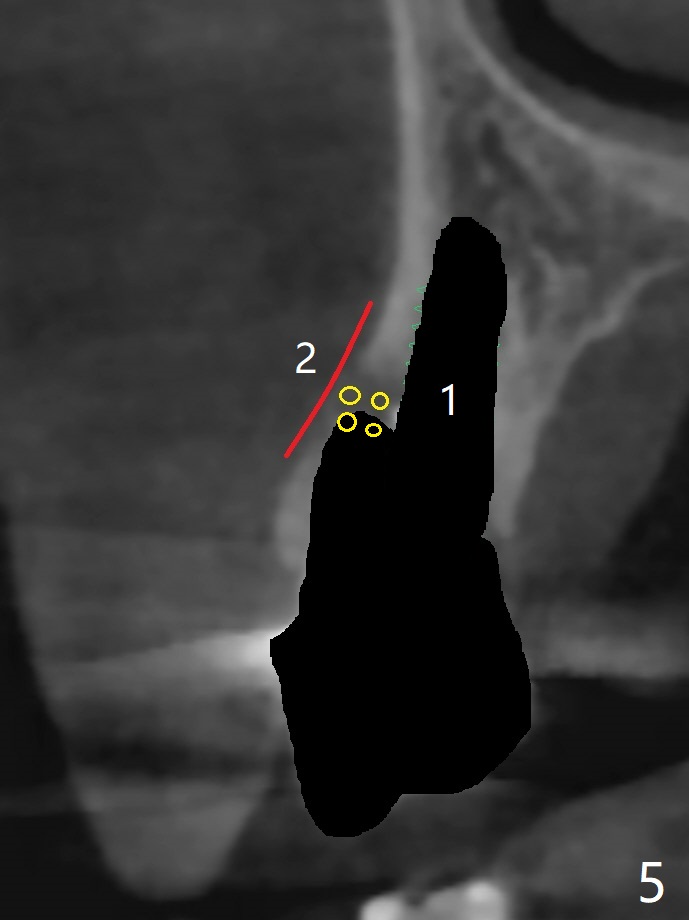

A 74-year-old woman is concerned about buccal fistula of the tooth #5 (Fig.1,2 >). It seems to be safe to place an immediate implant without too much possibility of developing periimplantitis in the future (Fig.3). With guide, restoration could be finished with a 15 degree angled abutment. Remove granulation tissue from the buccal fistula and from the socket. Place a piece of PRF membrane externally (tunnel incision, Fig.4-6 red line) or internally (from the socket) before bone graft (before and after implant placement (Fig.5,6 yellow circles)). Take 5x5 cm CT immediately postop to confirm the repair.